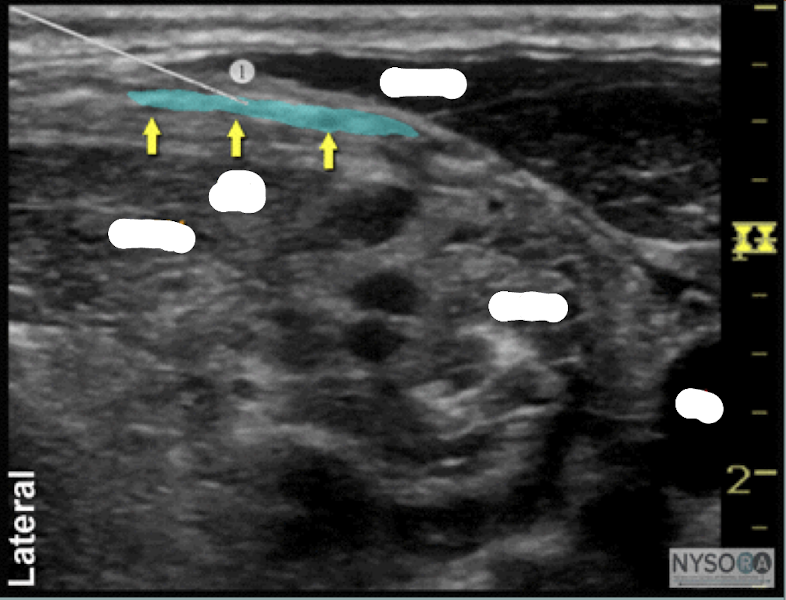

9

Q

Name the block and structures

A

transverse in plane PVB

pleural line

internal intercostal muscle

transverse process

How well did you know this?